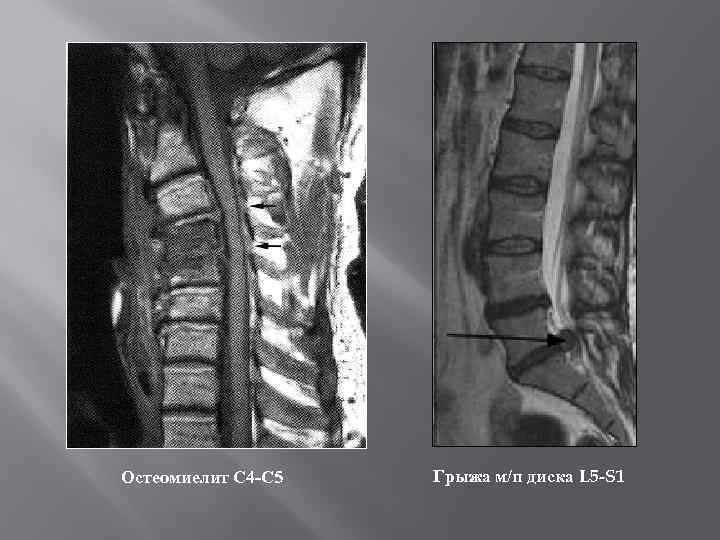

Остеомиелит С 4 -С 5 Грыжа м/п диска L 5 -S 1